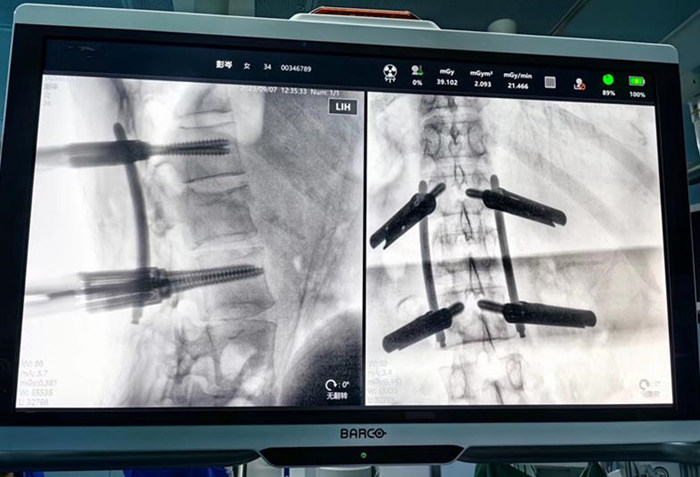

手术医师在机器人三维影像智能引导下,操作机械臂通过微创的方式,在脊柱上“打钉子”,使手术切口更小、损伤更小、出血更少、术后康复更快。术后影像显示,钉钉子的大小、位置、角度都接近完美。

术中透视见骨折复位完美,螺钉位置满意